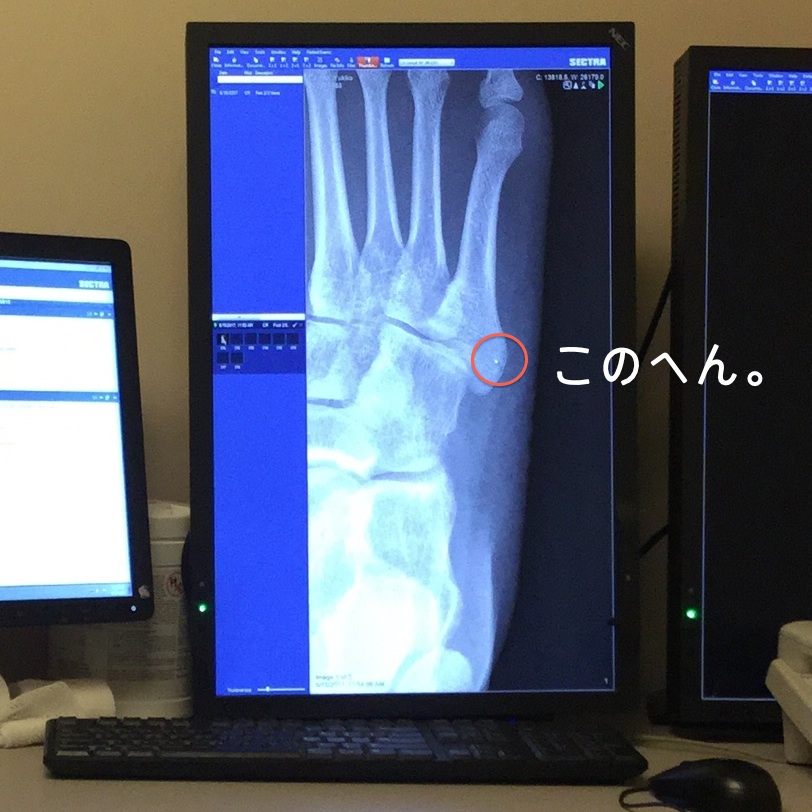

レントゲンを撮ってもらったら、実際はちっちゃなヒビがあった模様。ほぼ見えないけど。

骨の激写初公開☆